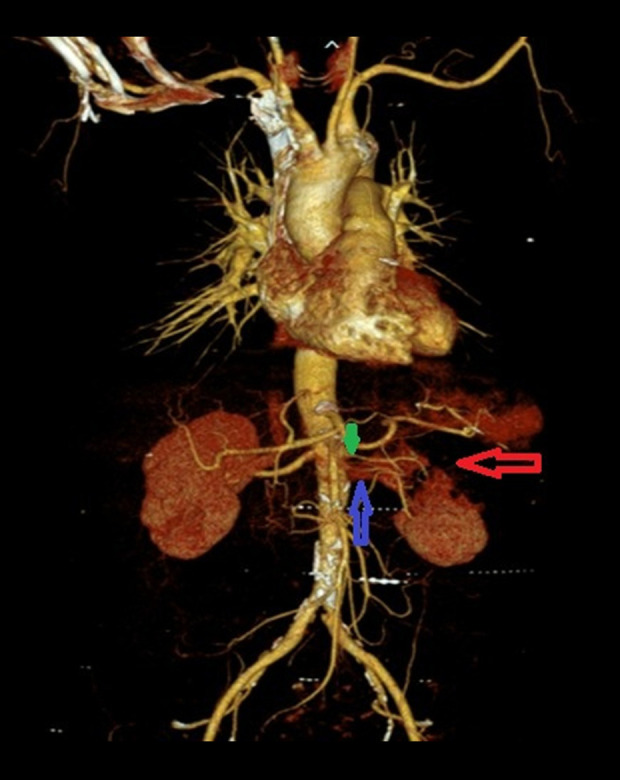

BACKGROUND Renal infarction is a rare condition resulting from interruption of renal arterial blood flow. Its nonspecific presentation often mimics more common diagnoses such as nephrolithiasis, pyelonephritis, or musculoskeletal pain, contributing to delayed or missed diagnosis. Early identification is essential to prevent irreversible renal damage and optimize patient outcomes. Imaging plays a critical role in both the initial diagnosis and in determining the underlying etiology, which may include thromboembolism, in-situ thrombosis, vascular injury, or hypercoagulable states. CASE REPORT We describe a case of a 63-year-old woman with a history of coronary artery disease, diabetes mellitus, hormone replacement therapy, and a 42 pack-year smoking history, who presented with sudden-onset, severe left-flank pain. Initial laboratory results were nonspecific, with mild proteinuria and microscopic hematuria. Computed tomography (CT) angiography demonstrated severe stenosis of the superior left renal artery and extensive left renal infarction. A diagnosis of atherosclerotic renal infarction was made. She was treated with intravenous heparin, transitioned to dual antiplatelet therapy and high-intensity statin, and discharged with a 30-day cardiac event monitor. No arrhythmia was detected, and her thrombophilia workup was negative. Follow-up CT angiography 1 month later revealed complete resolution of the renal artery stenosis, with no residual narrowing or plaque. The transient nature of the vascular finding, along with the lack of structural atherosclerosis, prompted diagnostic reassessment, favoring an embolic mechanism possibly related to multiple modifiable prothrombotic clinical risk factors and unrecognized embolic sources. CONCLUSIONS This case illustrates the importance of follow-up imaging and clinical reassessment in differentiating embolic from atherosclerotic causes of renal infarction.